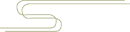

髌骨骨折只占全身骨折的 1%,治疗方式的选择和并发症的防治尤其要注意,急诊来了髌骨骨折患者,你怎么处理?髌骨是人体最大的籽骨,位于膝关节伸膝装置内。解剖特点包括近端宽大的基底和关节外的远侧尖端,前面位于关节外,后面为关节面。股直肌和股中间肌止于髌骨基底部,股内侧肌和股外侧肌止于髌骨的两侧。髌腱起于髌骨尖端,止于胫骨结节。髌骨骨折约占所有骨折的 1%,主要由直接暴力造成,如跌倒时跪地或膝关节屈曲时受到打击。典型的体征包括关节肿胀、压痛、伸膝功能部分或完全丧失。除以主诉和典型体征外,膝关节 X 线片也是必不可少的一项辅助检查,以膝关节正侧位 X 线片最常见,如果怀疑纵向骨折,膝关节屈曲 45° 时髌骨 30° 切位片可以辅助诊断。对于骨折不愈合、畸形愈合所致的关节面不平整以及髌股关节对应关系不良可采用 CT 检查。MRI 有助于诊断软骨缺损和损伤。34-B 型(部分关节内骨折,伸膝装置完整,如纵行骨折)髌骨下极骨折袢钢板结合克氏针、张力带固定 图源:作者提供